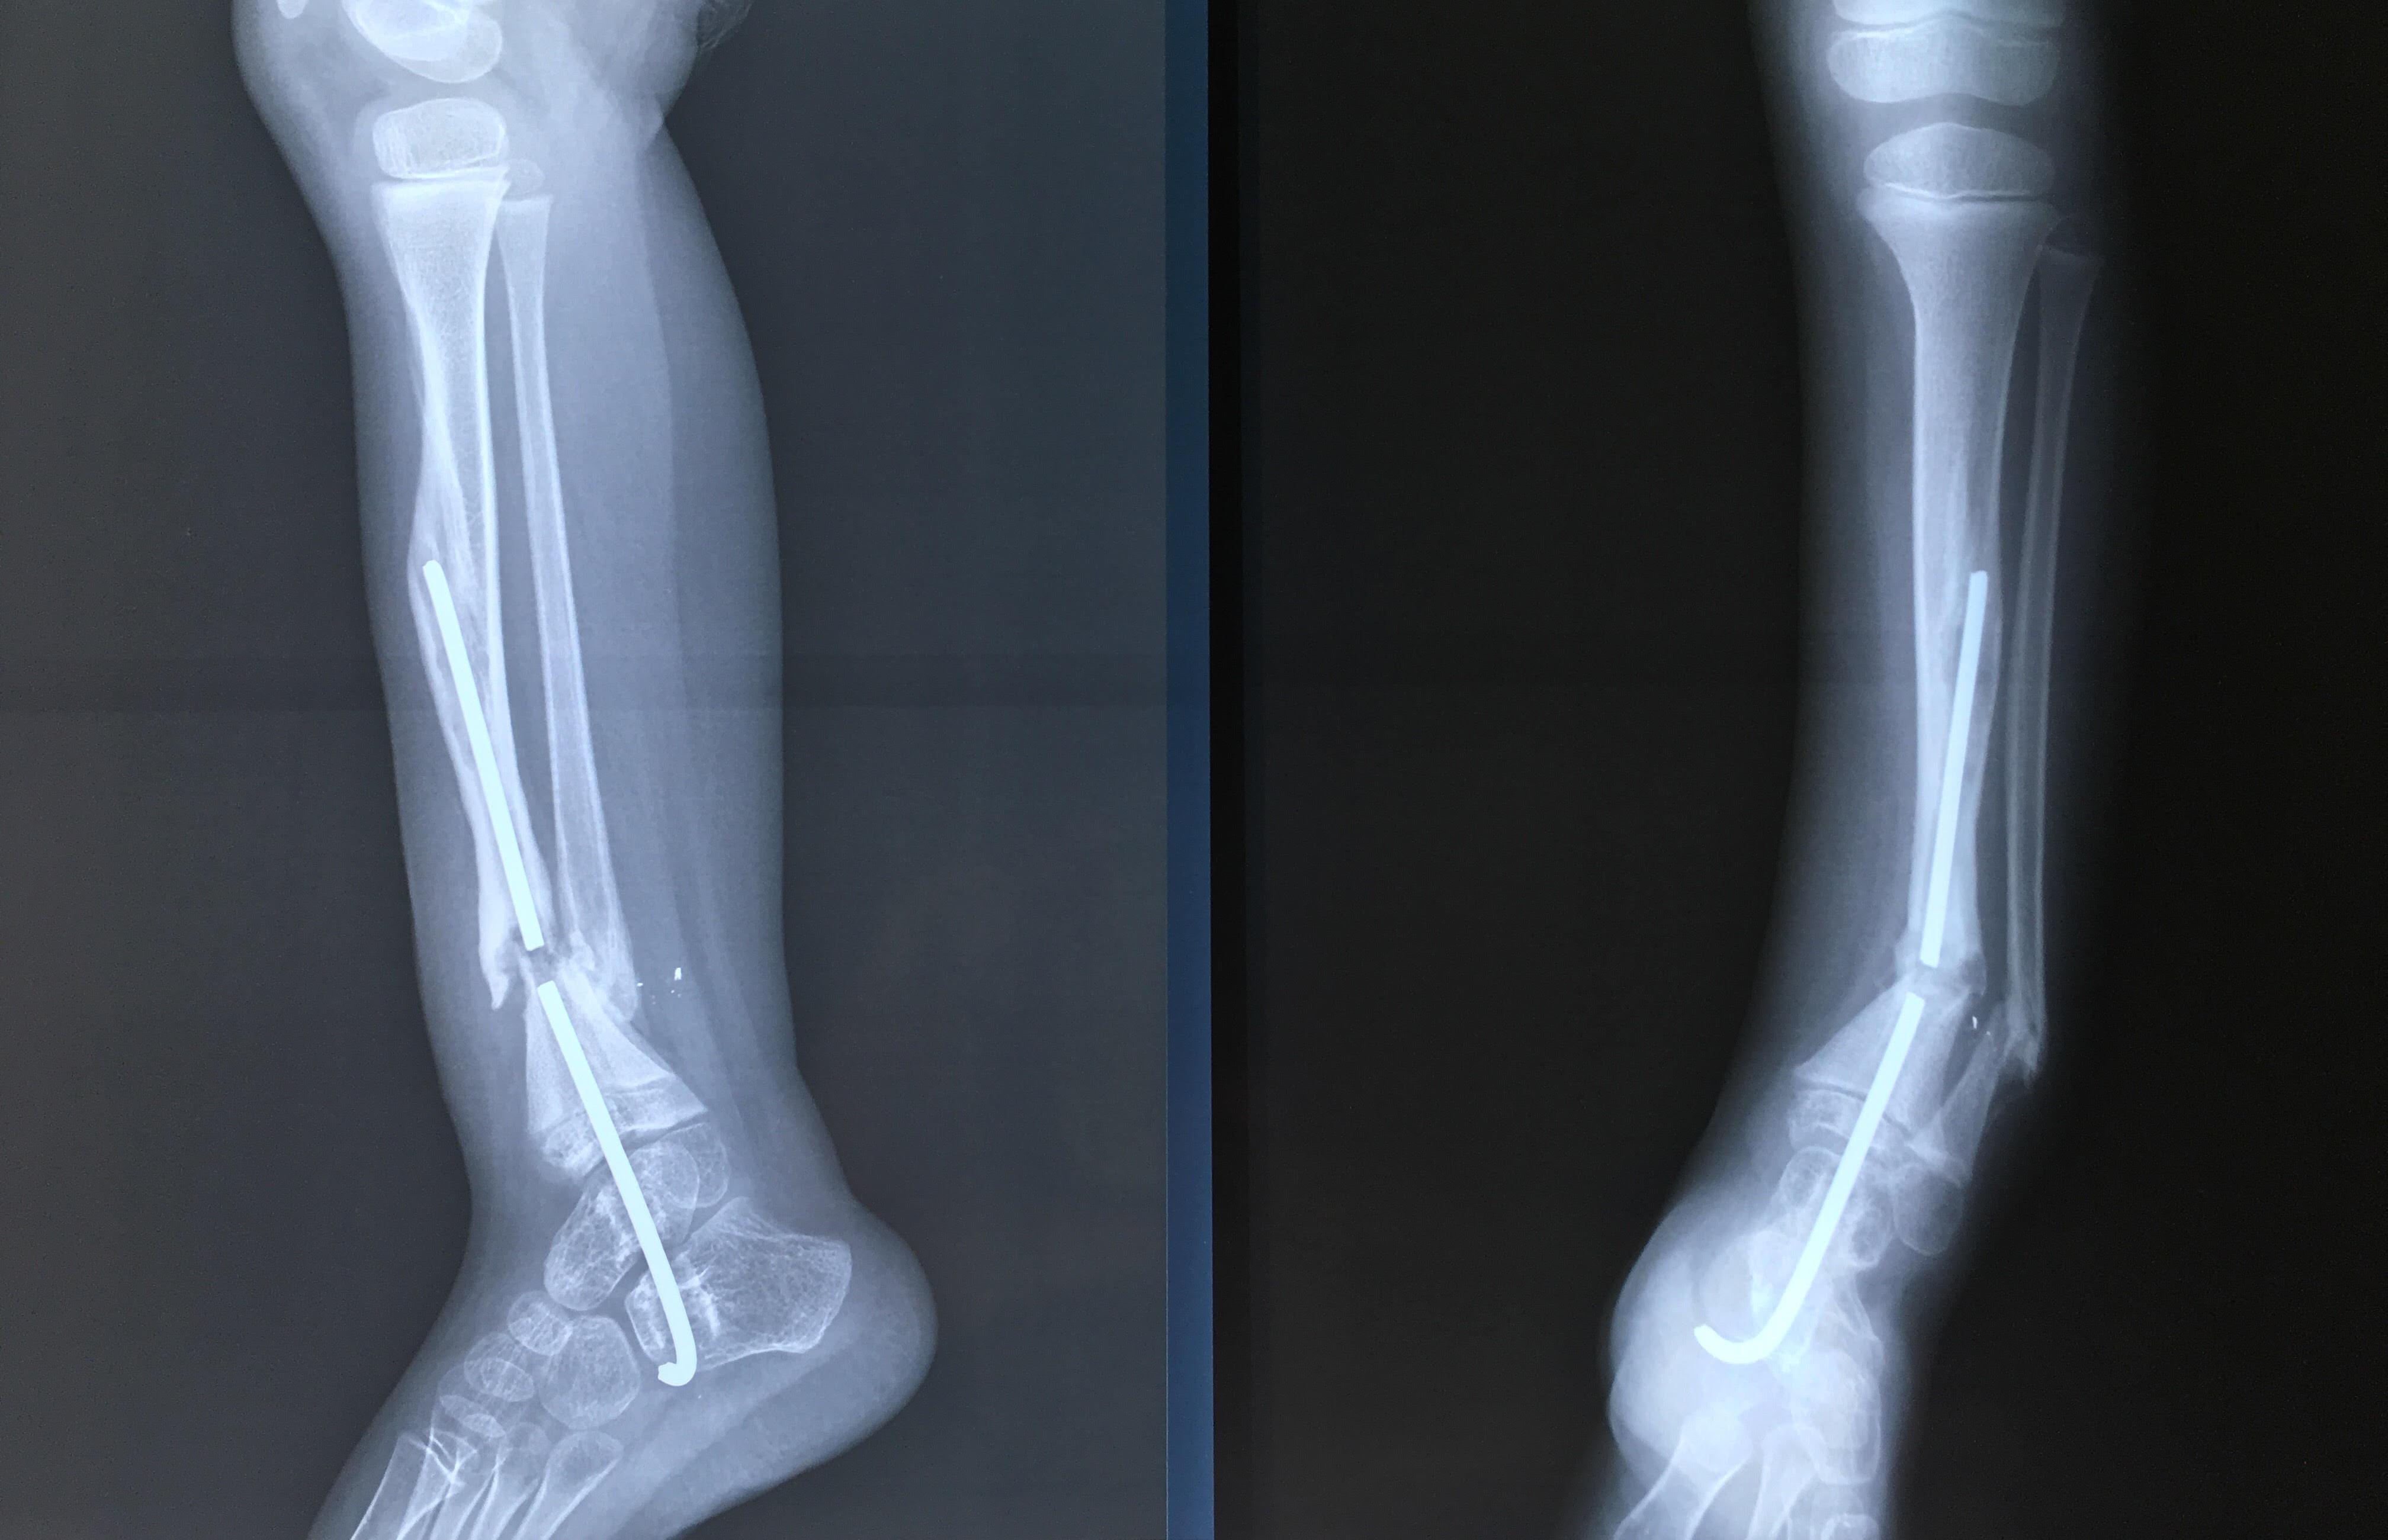

Phẫu thuật thành công ca bệnh hiếm gặp...khớp giả bẩm sinh xương chày

26/06/2019 17:00

Đã xem: 3534

Bệnh viện Chấn thương- Chỉnh hình Nghệ An, vừa phẫu thuật thành công cho bệnh nhi khớp giả bẩm sinh xương chày